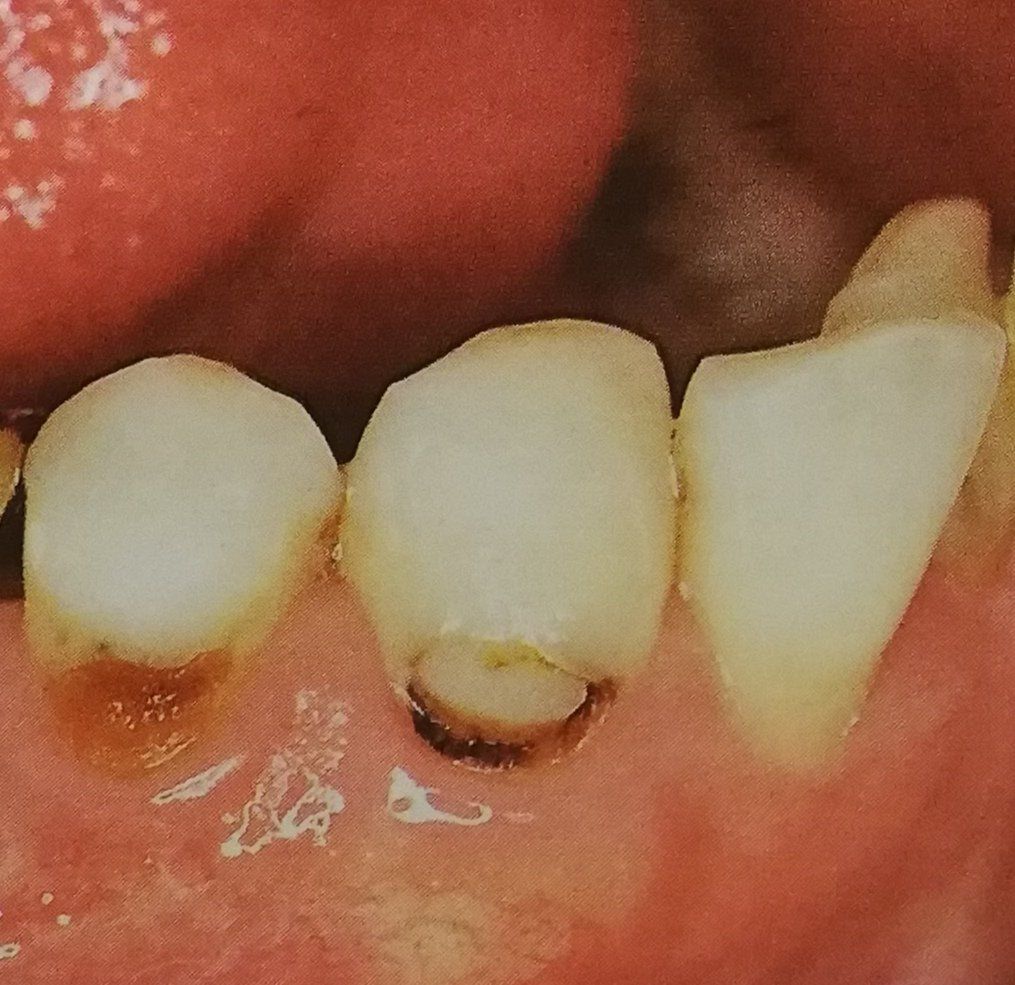

L’endodonzia si occupa della diagnosi e del trattamento dei problemi della polpa dentale, cioè la parte interna del dente, il trattamento più comune è la devitalizzazione, necessaria quando la polpa è infiammata o infetta a causa di carie profonde, traumi o lesioni.

Grazie alle moderne tecnologie usate dalla dott.ssa Lombardi Paola Daniela, l’intervento è rapido, indolore e permette di salvare sia il dente naturale evitandone l’estrazione, che radici residue utilizzabili come pilastri per capsule.

L'odontoiatria conservativa è finalizzata principalmente alla cura della carie dentale. L'obiettivo finale è quello di conservare l’elemento dentario compromesso ripristinandone la forma e il colore originario, per ottenere ciò ci si può avvalere sia di restauri diretti che indiretti.